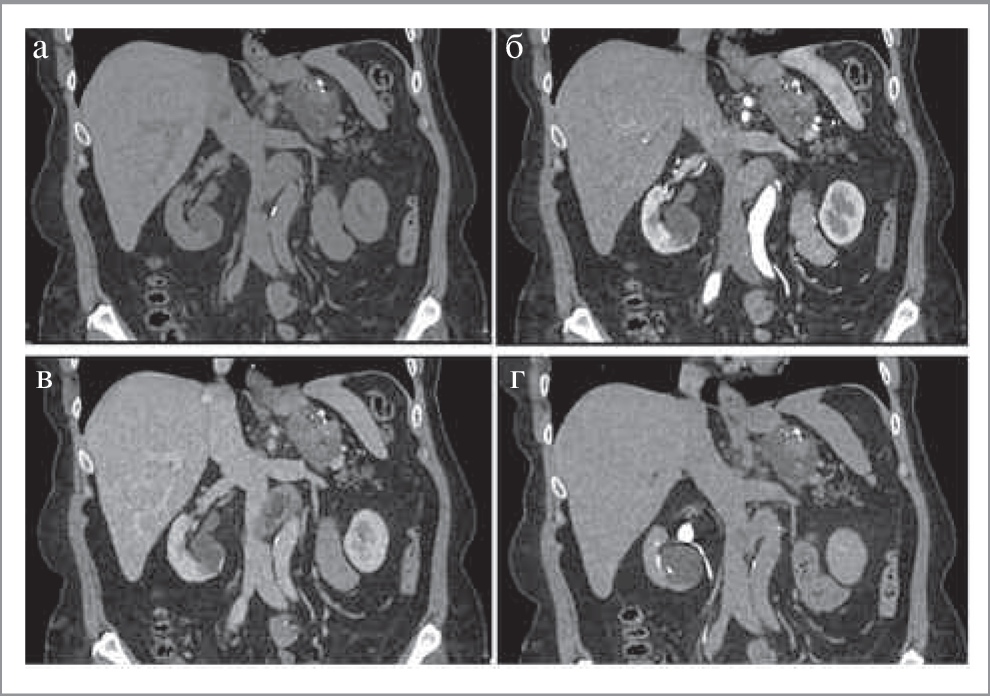

Рис. 6. МСКТ, аксиальная проекция: а – НФ; б – АФ; в – ВФ; г – ОФ. Параганглиома (стрелка).

КТ-картина феохромоцитом имеет различные признаки. Размер может варьировать от 1,2 до 15 см, в среднем около 5 см. Небольшие образования чаще однородны, в то время как более крупные часто неоднородны с участками жидкостной плотности (зонами некроза), зонами кровоизлияний, внутренними перегородками, а также обызвествлениями. Большинство опухолей интенсивно накапливает контрастный препарат в АФ с последующим умеренным его вымыванием к ОФ. Контуры образования, как правило, четкие, ровные за счет наличия капсулы (рис. 6). В редких случаях феохромоцитомы могут иметь включения макроструктурного жира, что также характерно и для миелолипом [16].

Озлокачествление опухоли наблюдается в 11% случаев у спорадических феохромоцитом и в 35% случаев наследственных феохромоцитом [19]. Выявление метастазов (чаще в костях, лимфатических узлах, легких и печени) подтверждает озлокачествление образования. Следует отметить, что, несмотря на то, что выраженное вымывание контрастного препарата для феохромоцитом нехарактерно, в редких случаях они могут иметь характеристики вымывания, аналогичные аденомам (APW более 60% и RPW более 40%), что затрудняет установку диагноза [16].